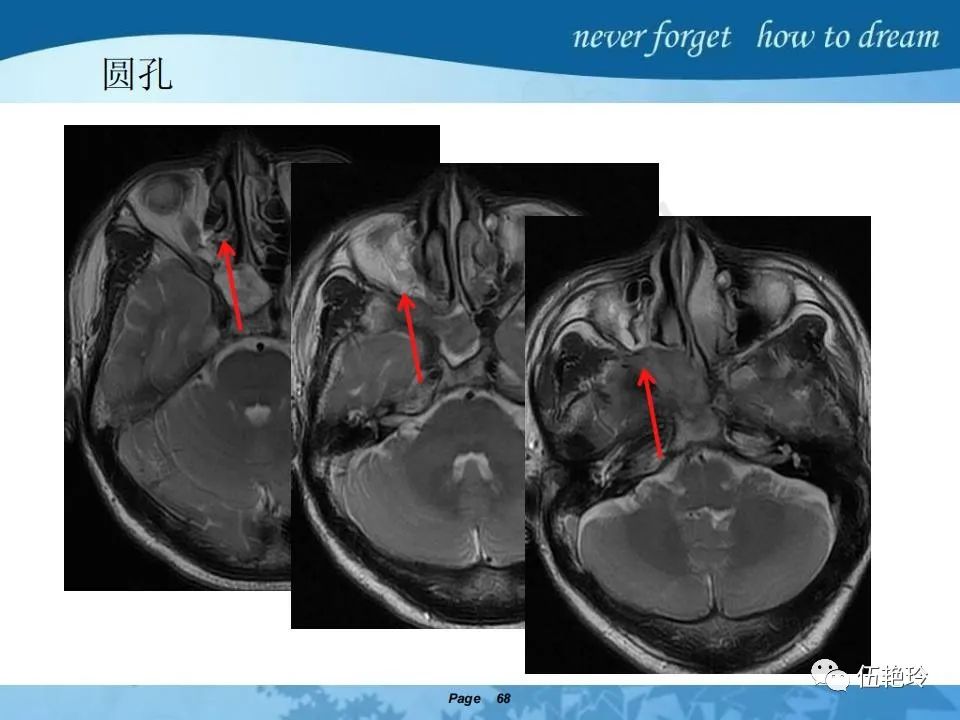

海绵窦区的解剖结构与鼻咽癌侵犯

2.31 向上颅内:①鼻咽顶壁→破裂孔(岩尖、斜坡)→蝶窦、海绵窦;②鼻咽顶壁→蝶骨基底部→蝶窦、海绵窦;③鼻咽侧壁→茎突前间隙→蝶骨大翼(卵圆孔)→海绵窦;④鼻咽侧壁→茎突前间隙→翼腭窝→ 颞下窝;⑤鼻咽前壁→鼻腔→翼突、翼腭窝→眶下裂→眶尖→海绵窦;⑥鼻咽前壁→鼻腔→上颌窦、筛窦;